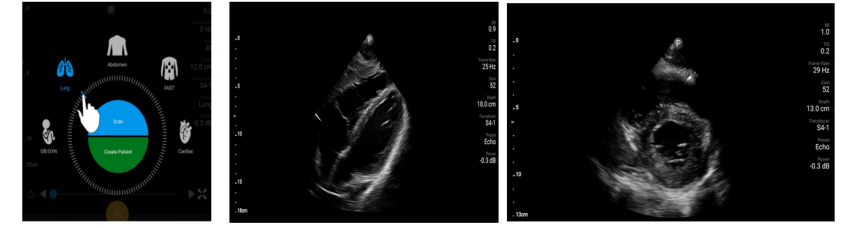

Chison Sonoeye P3 – phased array transducer with a frequency of 1.5 - 4.0 MHz and programs for the abdomen, cardiac, lung examinations.

Philips Lumify S4-1 - phased array transducer with a frequency of 1.0 - 4.0 MHz and a scanning depth up to 30 cm. It has programs for FAST, cardiac, lung, abdominal, obstetrics and gynecology examinations.

Here are some clinical images from which you can evaluate the quality of visualization and the interface of the program.